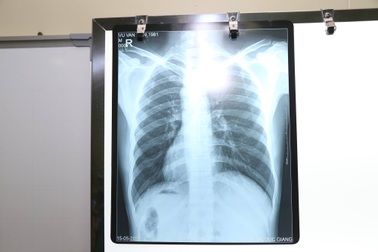

Kỳ lạ bệnh nhân có trái tim, nội tạng đảo ngược với người bình thườngHình ảnh chụp X - quang cho thấy bệnh nhân Vũ Văn H. (37 tuổi, Gia Lâm, Hà Nội) có trái tim cùng với các phủ tạng khác trong lồng ngực và bụng có vị trí "soi gương" so với bình thường. Tức là, trái tim và dạ dày ở bên phải, còn gan và ruột thừa thì ở bên trái.